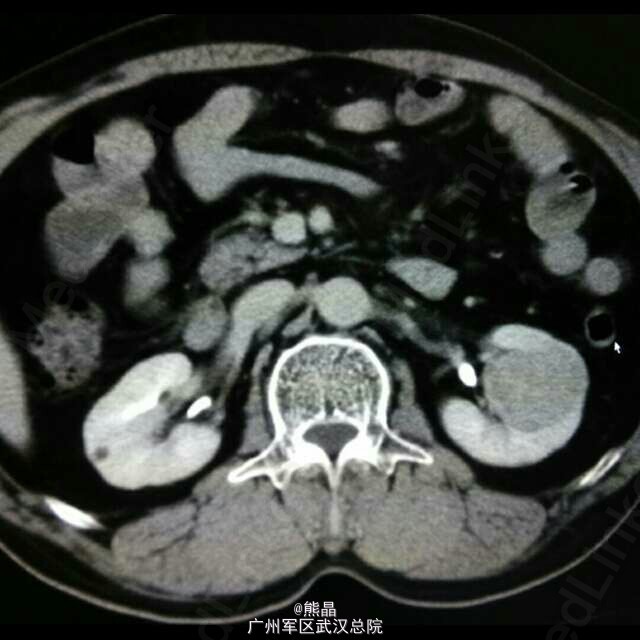

肾脏嗜酸性细胞瘤

患者男性,61岁,体检发现左肾占位病变5天,无明显临床症状。 肾脏嗜酸性细胞瘤是一种少见的肾脏良性肿瘤,与肾癌鉴别较困难。 肾脏嗜酸性细胞瘤增强扫描可以出现轮辐状强化,是其特征之一,肿瘤中可见星状瘢痕,为纤维母细胞增生,如肿瘤中有钙化,可以除外嗜酸。